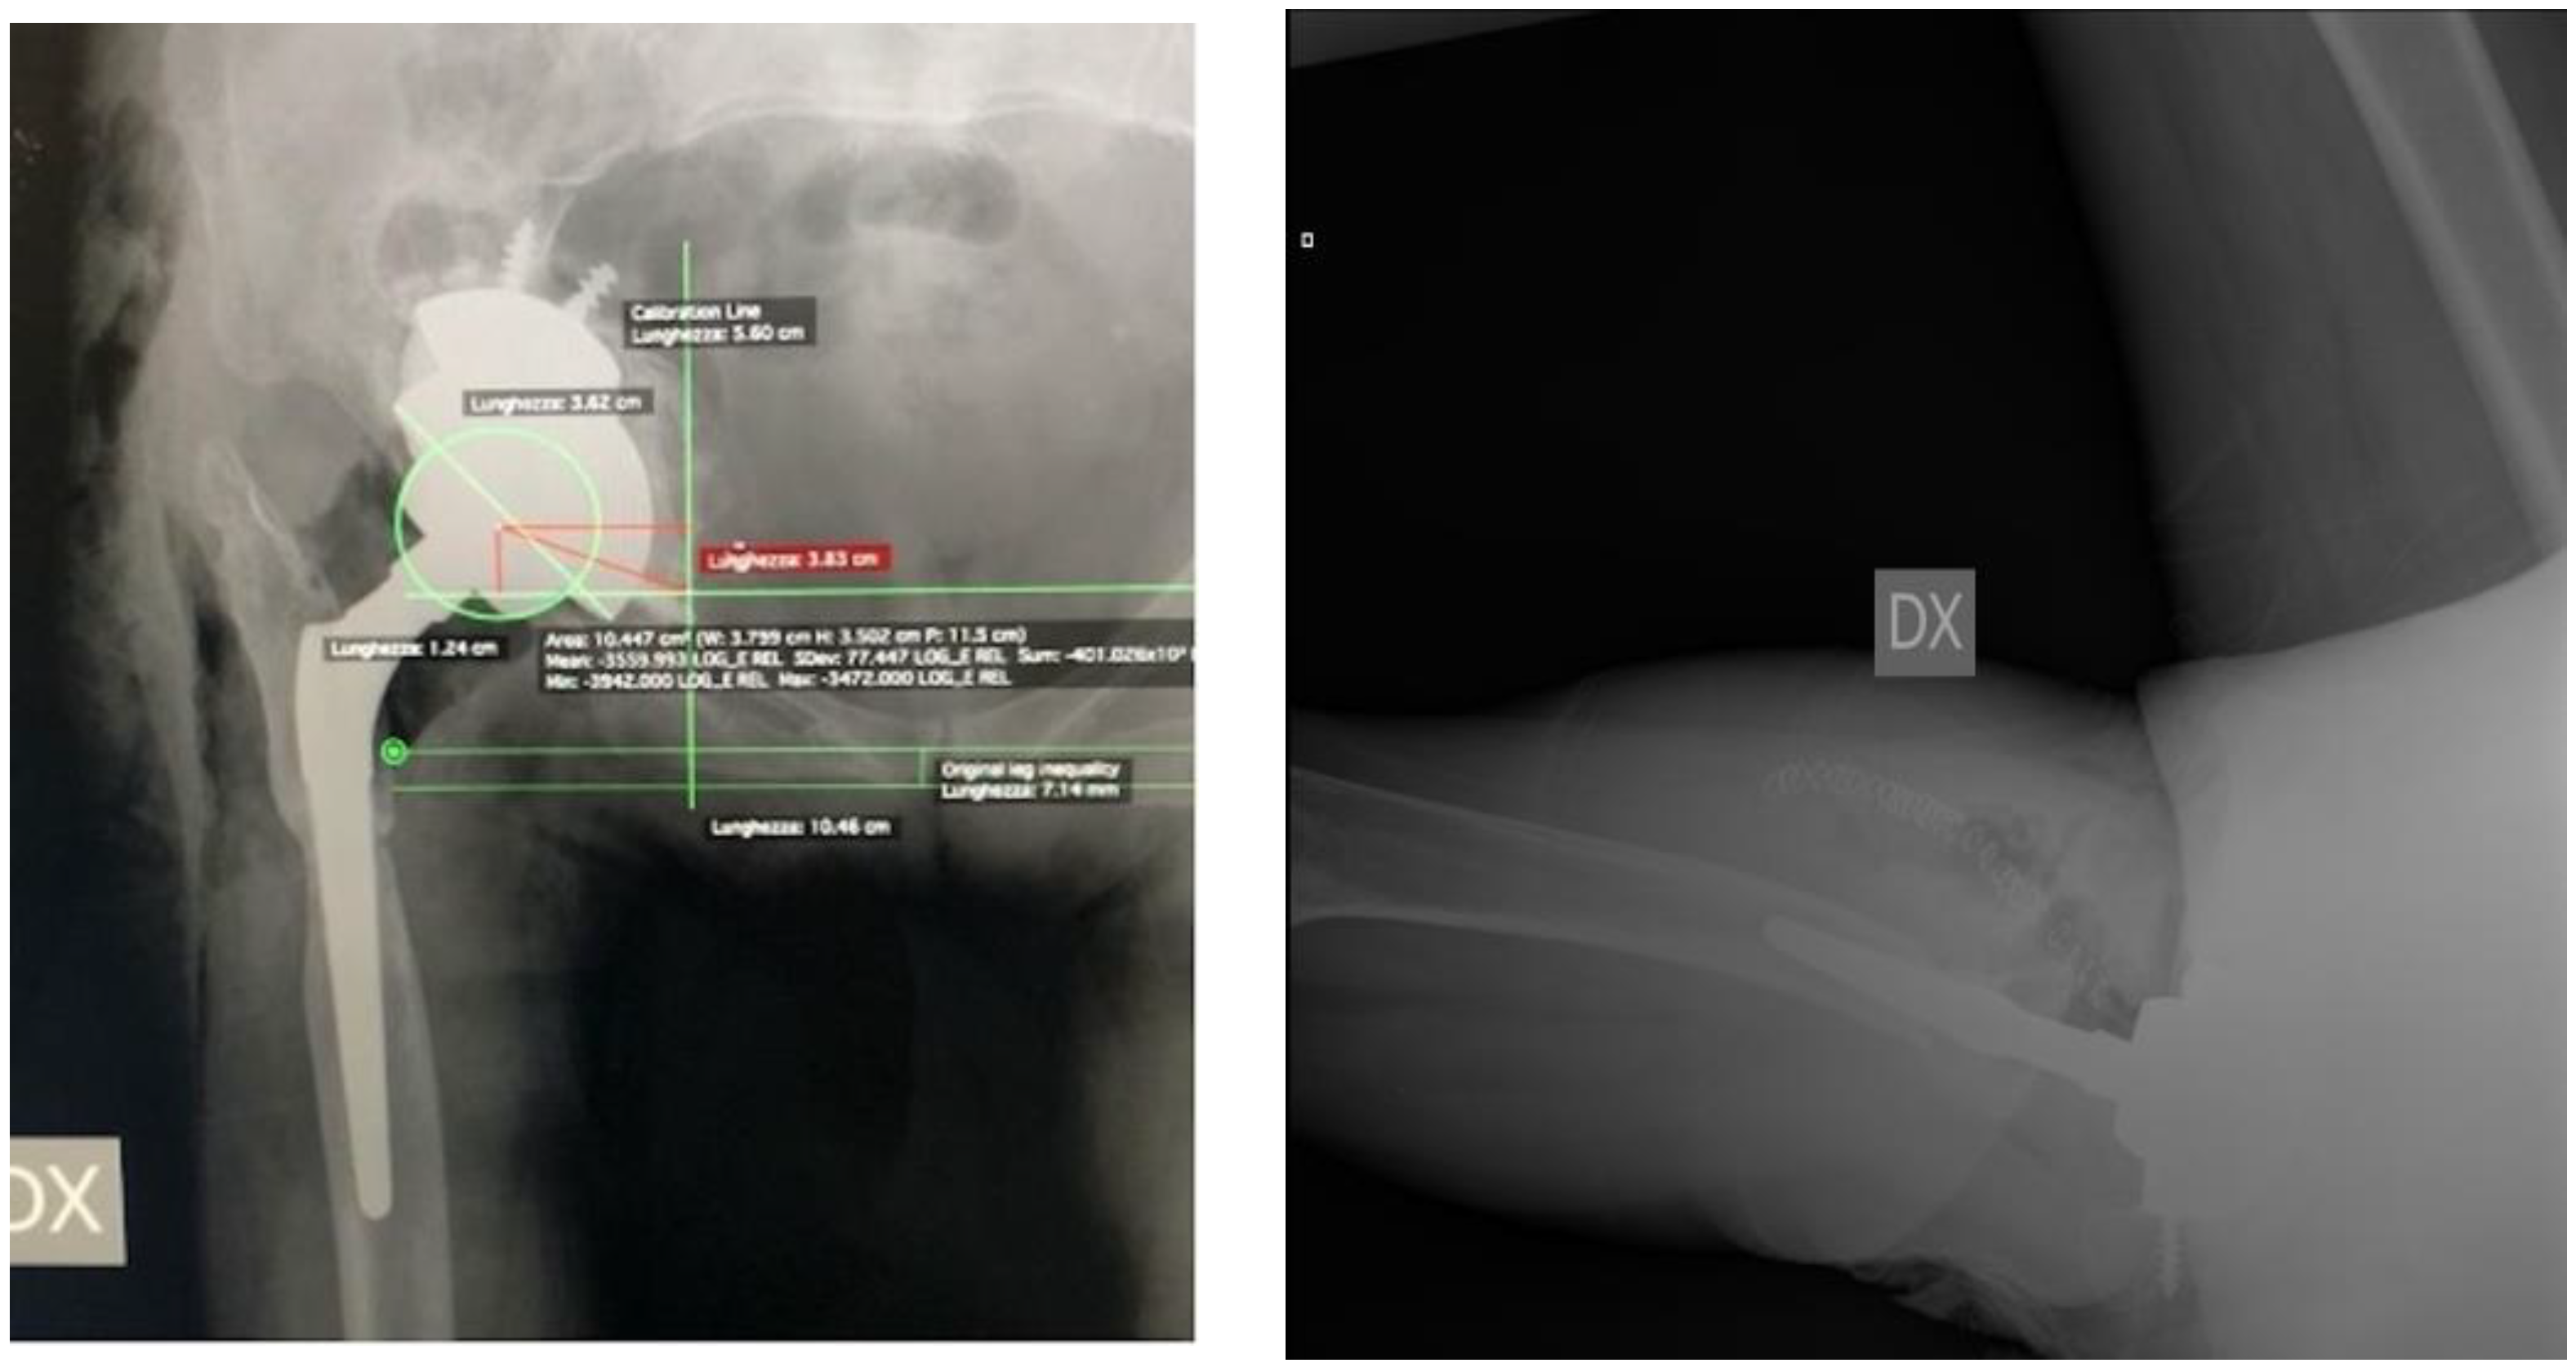

| LLD (cm) | 2.0 ± 1.2 | 0.6 ± 0.6 | p < 0.001 |

| Average COR vertical position (cm) | 3.5 ± 1.7 | 2.0 ± 0.7 | p < 0.05 |

| Average COR horizontal position (cm) | 3.9 ± 1.5 | 3.2 ± 0.5 | p < 0.05 |

| Acetabular component abduction angle | 59.7 ± 29.6 | 46.0 ± 3.9 | p < 0.05 |